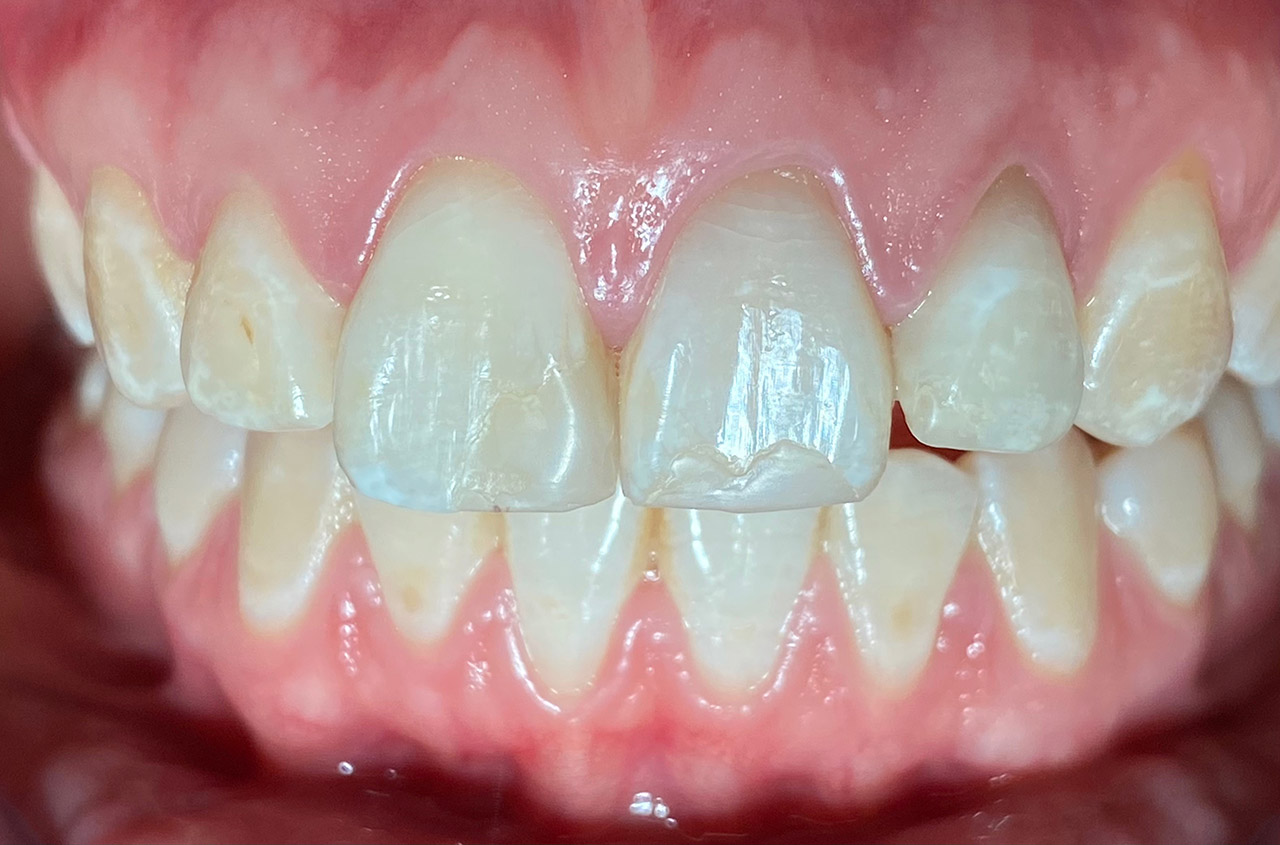

Internes und Externes Bleaching (Bleichen):

Nach Unfall mit E-Scooter unbefriedigendes Ergebnis der Erstversorgung (alio loco). Therapievorschlag: Stiftzähne?

Unsere minimalinvasive Therapie: Revision der Wurzelbehandlungen, danach internes und externes Bleaching, adhäsive Kunststoffüllungen in Schichttechnik. (Titel meiner Diplomarbeit 2003 “Die Vermeidung von Extraktion und Wurzelspitzenresektion durch zeitgemässe Endodontie in der Privatpraxis”)